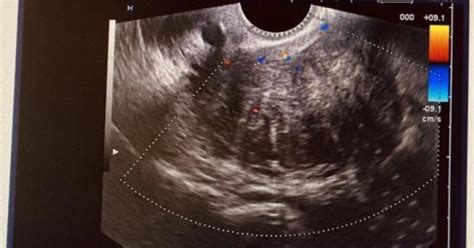

- Ecografia transvaginală: Metoda principală de diagnostic, ce permite vizualizarea formațiunilor tumorale, chiar și de mici dimensiuni.